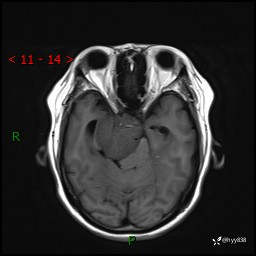

颅脑MRI平扫+增强